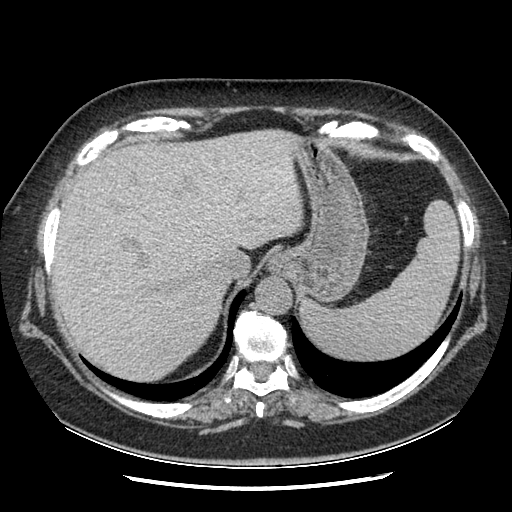

Reconstructed NATIVE CT scan (cycle consistency)

Full window (WL 1023.5, WW 4095 → Low −1024, High +3071)

Actual HU range: [-798.0, 546.5]